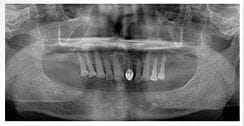

X 光片

術前X光片